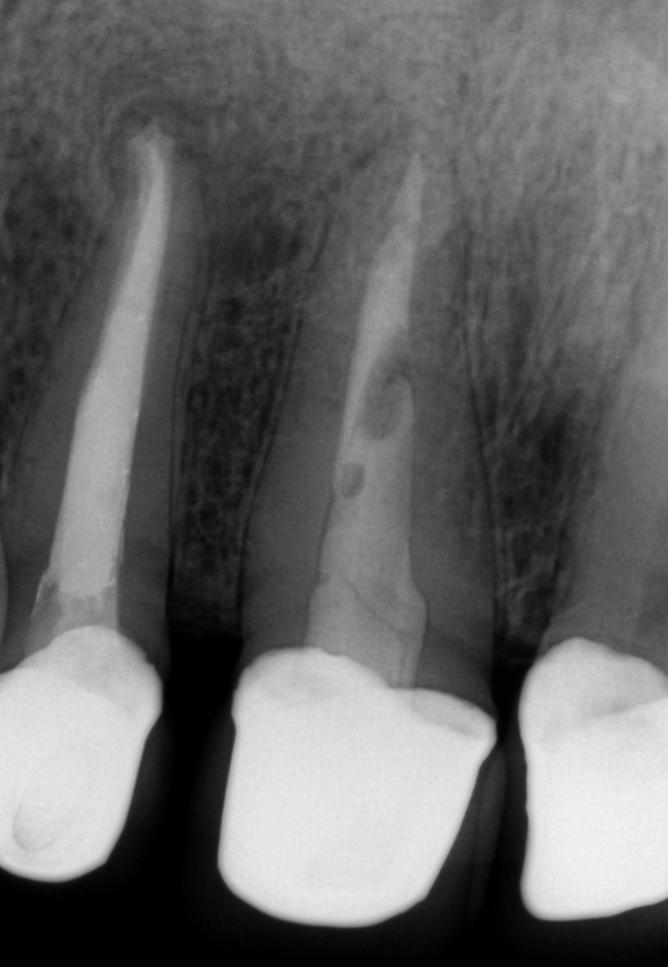

Leczenie endodontyczne – efekt przed i po

Stan przed leczeniem:

Na zdjęciu RTG widoczna rozległa zmiana okołowierzchołkowa, klinicznie czynna przetoka, świadcząca o przewlekłym stanie zapalnym tkanek otaczających korzeń zęba.

Wykonano powtórne leczenie kanałowe (rewizję endodontyczną), polegające na usunięciu starego materiału, dokładnym oczyszczeniu i dezynfekcji kanałów oraz ich szczelnym wypełnieniu z wykorzystaniem nowoczesnych technologii.